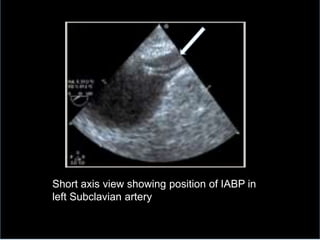

 TOE

direct visualisation 1-2cm distal to the left

subclavian artery

Short axis view showing position of IABP tip

too high to Left Subclavian artery orifice

Short axis view showing position of IABP in

left Subclavian artery